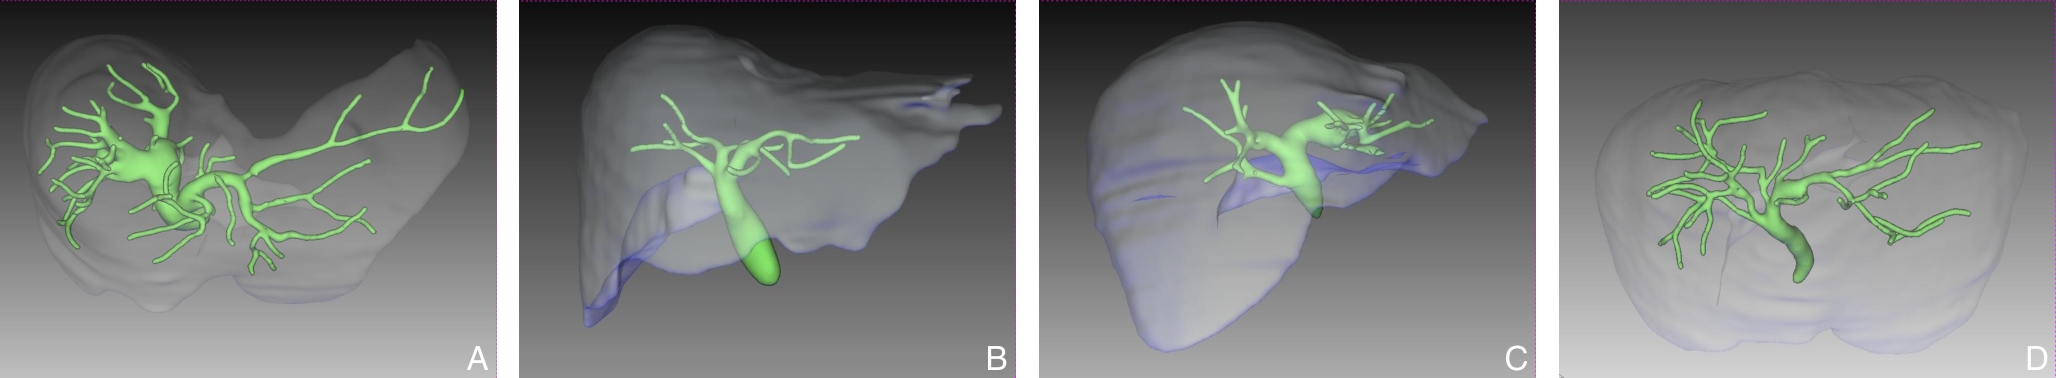

Background and Aims Precise identification and control of segmental Glissonian pedicles are fundamental to laparoscopic anatomical liver segmentectomy. However, marked anatomical variations, particularly in the right hemiliver, pose significant technical challenges. Based on the anatomical concept of the hepatic Laennec's membrane, this study aimed to systematically investigate the applied anatomy of Glissonian pedicles at the hepatic hilum and to establish practical anatomical landmarks for laparoscopic anatomical liver resection.Methods Six intact adult human liver specimens without macroscopic lesions were dissected under the guidance of the Laennec's membrane concept. The segmental Glissonian pedicles at the first porta hepatis were meticulously isolated, and the intervening liver parenchyma was removed. The origin, branching patterns, and spatial courses of Glissonian pedicles in each hepatic segment were analyzed. For the right hemiliver, a localization system consisting of four anatomical landmarks, two reference lines, and four characteristic angles was proposed and quantitatively evaluated using specimen measurements combined with CT imaging and three-dimensional liver reconstruction.Results The intrahepatic Glissonian system demonstrated both consistent patterns and pronounced individual variations. In the left hemiliver, the Glissonian pedicles of segments Ⅱ and Ⅲ usually arose independently, while segment Ⅳ commonly presented a bifurcated pattern with occasional multiple branches. In contrast, the right hemiliver showed substantial variability: segment V pedicles were frequently multibranched and often received contributions from segment Ⅵ; segment Ⅵ served as a pivotal pedicle with multiple branches contributing to segments V and Ⅶ; segment Ⅶ most commonly originated from the root of the right posterior pedicle, although in some cases it was formed by distal extensions of segment Ⅵ; segment Ⅷ pedicles were relatively constant in morphology, typically consisting of one or two branches. The proposed anatomical landmarks and quantitative parameters enabled clearer spatial localization of segmental Glissonian pedicles in the right liver.Conclusion Systematic dissection of segmental Glissonian pedicles guided by the Laennec's membrane concept, together with a quantitative anatomical landmark system, enhances the understanding of their spatial anatomy and variations. This approach provides practical and reliable anatomical guidance for precise and safe laparoscopic anatomical liver segmentectomy.

SHEN Zhengchao, CHEN Zhiyuan, XI Shihang, PAN Xuan, QIAN Daohai, MUHAMMAD Danish Irshad, WANG Xiaoming

Background and Aims Laparoscopic resection of centrally located hepatic tumors remains technically demanding due to the complex anatomical relationships with major vascular structures. Conventional intraoperative ultrasound or indocyanine green fluorescence imaging (ICG-FI) alone has limitations, particularly in visualizing deep anatomical structures. This study aimed to evaluate the clinical value of augmented reality (AR) navigation combined with ICG-FI in laparoscopic resection of central hepatic tumors.Methods A retrospective analysis was conducted on 38 consecutive patients who underwent laparoscopic resection of central hepatic tumors guided by AR navigation combined with ICG-FI between May 2022 and March 2025. Intraoperative navigation performance, surgical parameters, and perioperative outcomes were assessed.Results All 38 procedures were completed laparoscopically without conversion. The intraoperative tumor fluorescence detection rate was 100%. The mean operative time was (324.9 ± 132.4) min, and the median intraoperative blood loss was 400 (50-1 200) mL. The mean registration error was (6.3±0.6) mm. The median number of predicted and verified vessels was 6 (4-8) and 7 (5-10), respectively. R0 resection was achieved in all patients, with a mean surgical margin of (1.5±0.5) cm. The postoperative complication rate was 13.2%, with no severe complications such as intra-abdominal hemorrhage, gas embolism, or liver failure. The median postoperative hospital stay was 9 (4-20) days. During a median follow-up of 20 months, no tumor recurrence was observed.Conclusion The combined use of AR navigation and ICG-FI enables intraoperative prediction and verification of critical vascular structures and facilitates precise control of the transection plane in laparoscopic resection of central hepatic tumors. This technique improves surgical precision and safety and shows promising clinical potential.